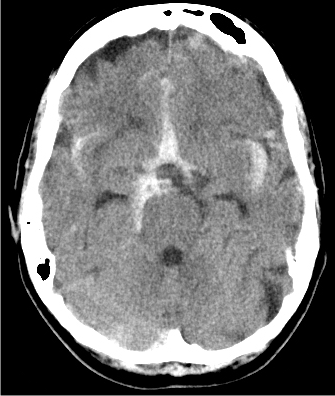

A 40-year-old man comes to the emergency department due to severe headache associated with photophobia and nausea for the past several hours. The patient reports mild cold symptoms a week ago. He has a 2-year history of hypertension and has smoked a pack of cigarettes daily for 15 years. His father died of stroke at the age of 75. Temperature is 37.7 C (100 F) , blood pressure is 170/100 mm Hg, and pulse is 92/min and regular. He appears to be uncomfortable and had an episode of nonbilious vomiting in the emergency department. Neurologic examination shows 4/5 motor strength and 2+ deep tendon reflexes bilaterally in the upper and lower extremities. Sensation to light touch and pinprick is normal. CT scan of the head without contrast is shown below.

Which of the following is the most likely cause of this patient's headache?